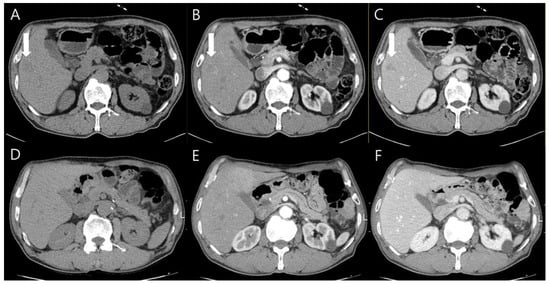

Chest contrast-enhanced CT revealed multiple peribronchial, centrilobular, and cavitary nodules in both lungs (Figure 2), and they have upper lung predominance. The radiologist considered this to be pulmonary metastasis from colorectal cancer first and an infectious condition second. Abdominal CT showed a 2 cm sized, ill-defined lesion in segment 5/6 of the liver (Figure 3). As a differential diagnosis for the solitary hepatic lesion, we considered sclerosing hemangioma, inflammatory pseudotumor, or metastasis. Laboratory results showed only a mild increase in the eosinophil ratio (6.6%). Except for that, no abnormalities were found in the coagulation system or general biochemical tests. Serologic markers for hepatitis B and C, acid-fast bacteria (AFB) stain, and AFP culture were negative. Regarding tumor markers, carcinoembryonic antigen and carbohydrate antigen 19-9 were normal. At that time, he did not take any medication or show signs of infection or other systemic symptoms such as fever or night sweats. In addition, his exact history of previously eating uncooked cow liver or meat is unclear.

Figure 3.

Abdominal CT images showed the solitary 2 cm ill-defined nodule in segment 5/6 of the liver ((A–C), arrows). It was presented as an ill-defined low-attenuation nodule in the pre-contrast phase (A), poorly delineated in the arterial phase (B), and also visible in the portal phase (C). After 6 months, the nodule was invisible in all phases (D–F).

Liver magnetic resonance imaging (MRI) was performed to differentiate the pulmonary and hepatic lesions from another possible diagnosis. It revealed a 1.5 cm ill-defined nodular lesion contiguously extending into the liver capsule (Figure 4). These findings mostly likely represented liver fluke disease. The diagnosis of toxocariasis was confirmed through the presence of antibodies to Toxocara canis by enzyme-linked immunoassay (ELISA). Other parasite antibody tests, including Clonorchiasis sinesis, Paragonimus westermani, Taenia solium, Spirometra mansoni, Fasciola hepatica, Amoeba, Trichinella spiralis, and Schistosoma, all yielded negative results. Eventually, his colon cancer was treated with laparoscopic low anterior resection. After discharge, the patient took oral albendazole by himself. After 3 months, chest and abdominal CT was performed for the postoperative routine follow-up, and it showed a shrinkage of all pulmonary and hepatic lesions compared to the previous imaging. Finally, after 5 months, the entire multiple cavitary lung and the hepatic nodules disappeared (Figure 2 and Figure 3). In addition, the eosinophil ratio decreased from 6.6% to 0.4%.